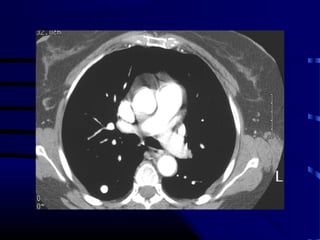

Question

• Patient is a 65 year old smoker with

following CXR and CT scan of chest:

• What test do we order next?